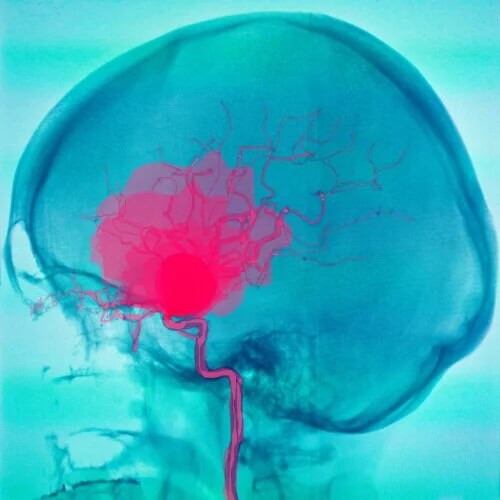

- Krwotoki: gdy dochodzi do pęknięcia tętnicy w mózgu krwotok tworzy skupisko krwi, które, jeśli znajduje się w pobliżu opon mózgowych, powoduje ich zapalenie. Skutkiem tego są objawy oponowe. Na początku objawów udar mózgu może być mylony z bakteryjnym zapaleniem opon mózgowych, m.in. z powodu obecności gorączki.

Udary mózgu mogą generować objawy oponowe z powodu gromadzenia się krwi w oponach mózgowych.